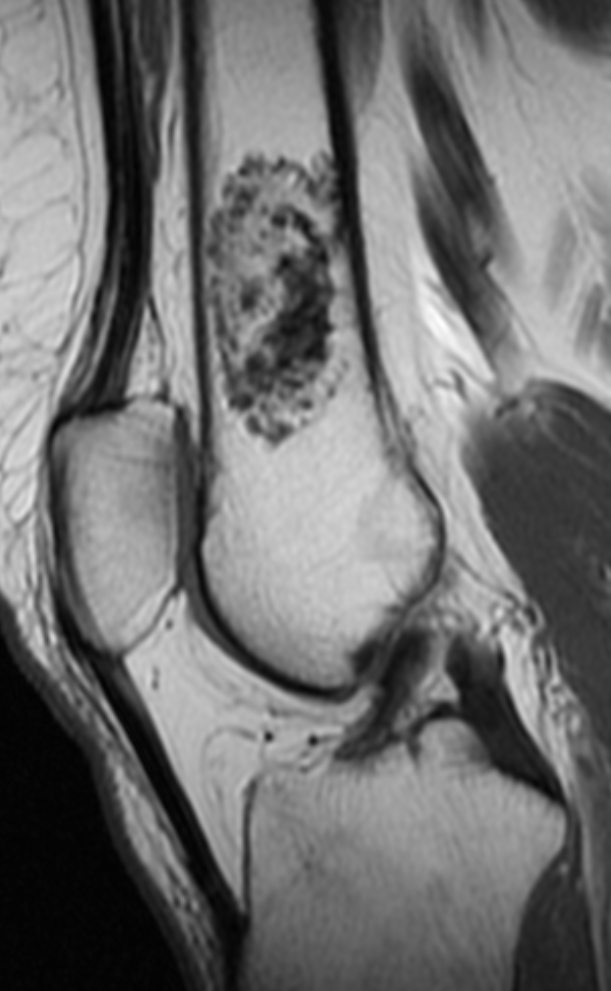

Магнитно-резонансная томография при энхондроме хорошо выявляет следующие анатомические признаки:

В режиме Т1 определяется гипоинтенсивный или изоинтенсивный сигнал от внутреннего содержимого опухоли по сравнению с костным мозгом, что отражает хондроидную природу образования.

В режиме Т2 визуализируется гиперинтенсивный сигнал от хрящевого матрикса, особенно выраженный в участках с высоким содержанием жидкости.

В режиме с подавлением сигнала от жира подчёркивается внутренняя структура опухоли, а также различие между опухолью и прилежащим костным мозгом.

В режиме с контрастированием наблюдается умеренное или кольцевидное накопление контраста по периферии опухоли, характерное для зрелого хондроидного матрикса.

Определяются признаки истончения кортикального слоя, лёгкой выпуклости наружного контура кости и отсутствие признаков инвазии в мягкие ткани.